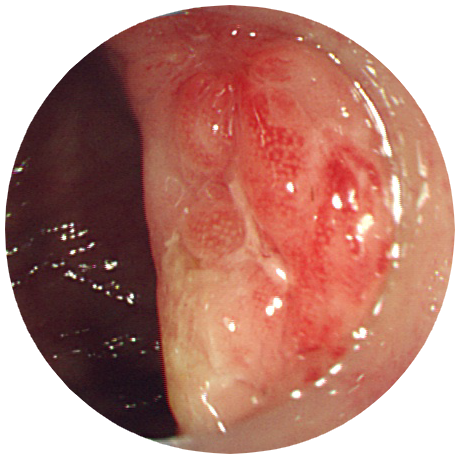

大腸疾患

S字結腸癌(全周性)

説明